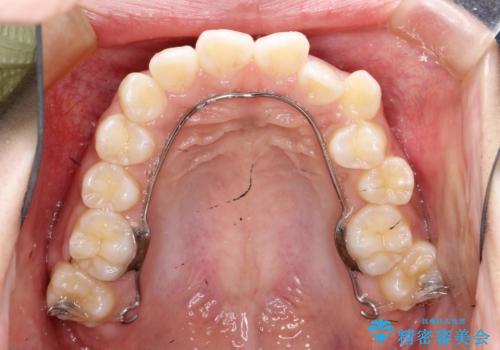

ハーフリンガル 半分裏側矯正による上下前突の抜歯矯正治療

- 矯正装置

- ハーフリンガル

- 上下左右4本の第1小臼歯を抜歯する、抜歯矯正を計画した。

抜歯矯正により前歯の位置が後ろに下がり、わずかではありますが、口元に改善がみられ、歯並びもきれいに整いました。